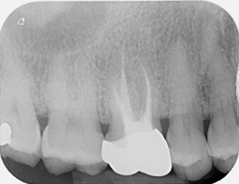

Root canal retreatment and bypass of separated instrument

Pre-op

12 month review demonstrating healing